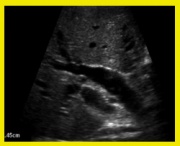

| 11:17, 27 במאי 2013 | Gallbladder14.jpg (קובץ) |  |

| 11:15, 27 במאי 2013 | Gallbladder6.jpg (קובץ) |  |

| 11:10, 27 במאי 2013 | Gallbladder5.jpg (קובץ) |  |

| 11:02, 27 במאי 2013 | Gallbladder4.jpg (קובץ) |  |

| 11:00, 27 במאי 2013 | Gallbladder3.jpg (קובץ) |  |

| 10:59, 27 במאי 2013 | Gallbladder2.jpg (קובץ) |  |

| 10:57, 27 במאי 2013 | Gallbladder1.jpg (קובץ) |  |

| 04:13, 23 במאי 2013 | Gallbladder13.jpg (קובץ) |  |